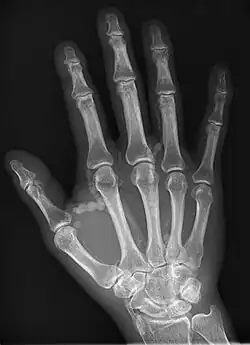

| Hand radiograph showing tumoral calcinosis, PA radiograph of the right hand showing tumoral calcinosis-like metastatic calcification in a patient on dialysis. Dialysis alters calcium phosphate product (>70). Idiopathic tumoral calcinosis is autosomal dominant and is not associated with dialysis. Note the premature arterial calcification which is a clue that this is a renal patient. Vascular calcification contributes to an increase in morbidity. |